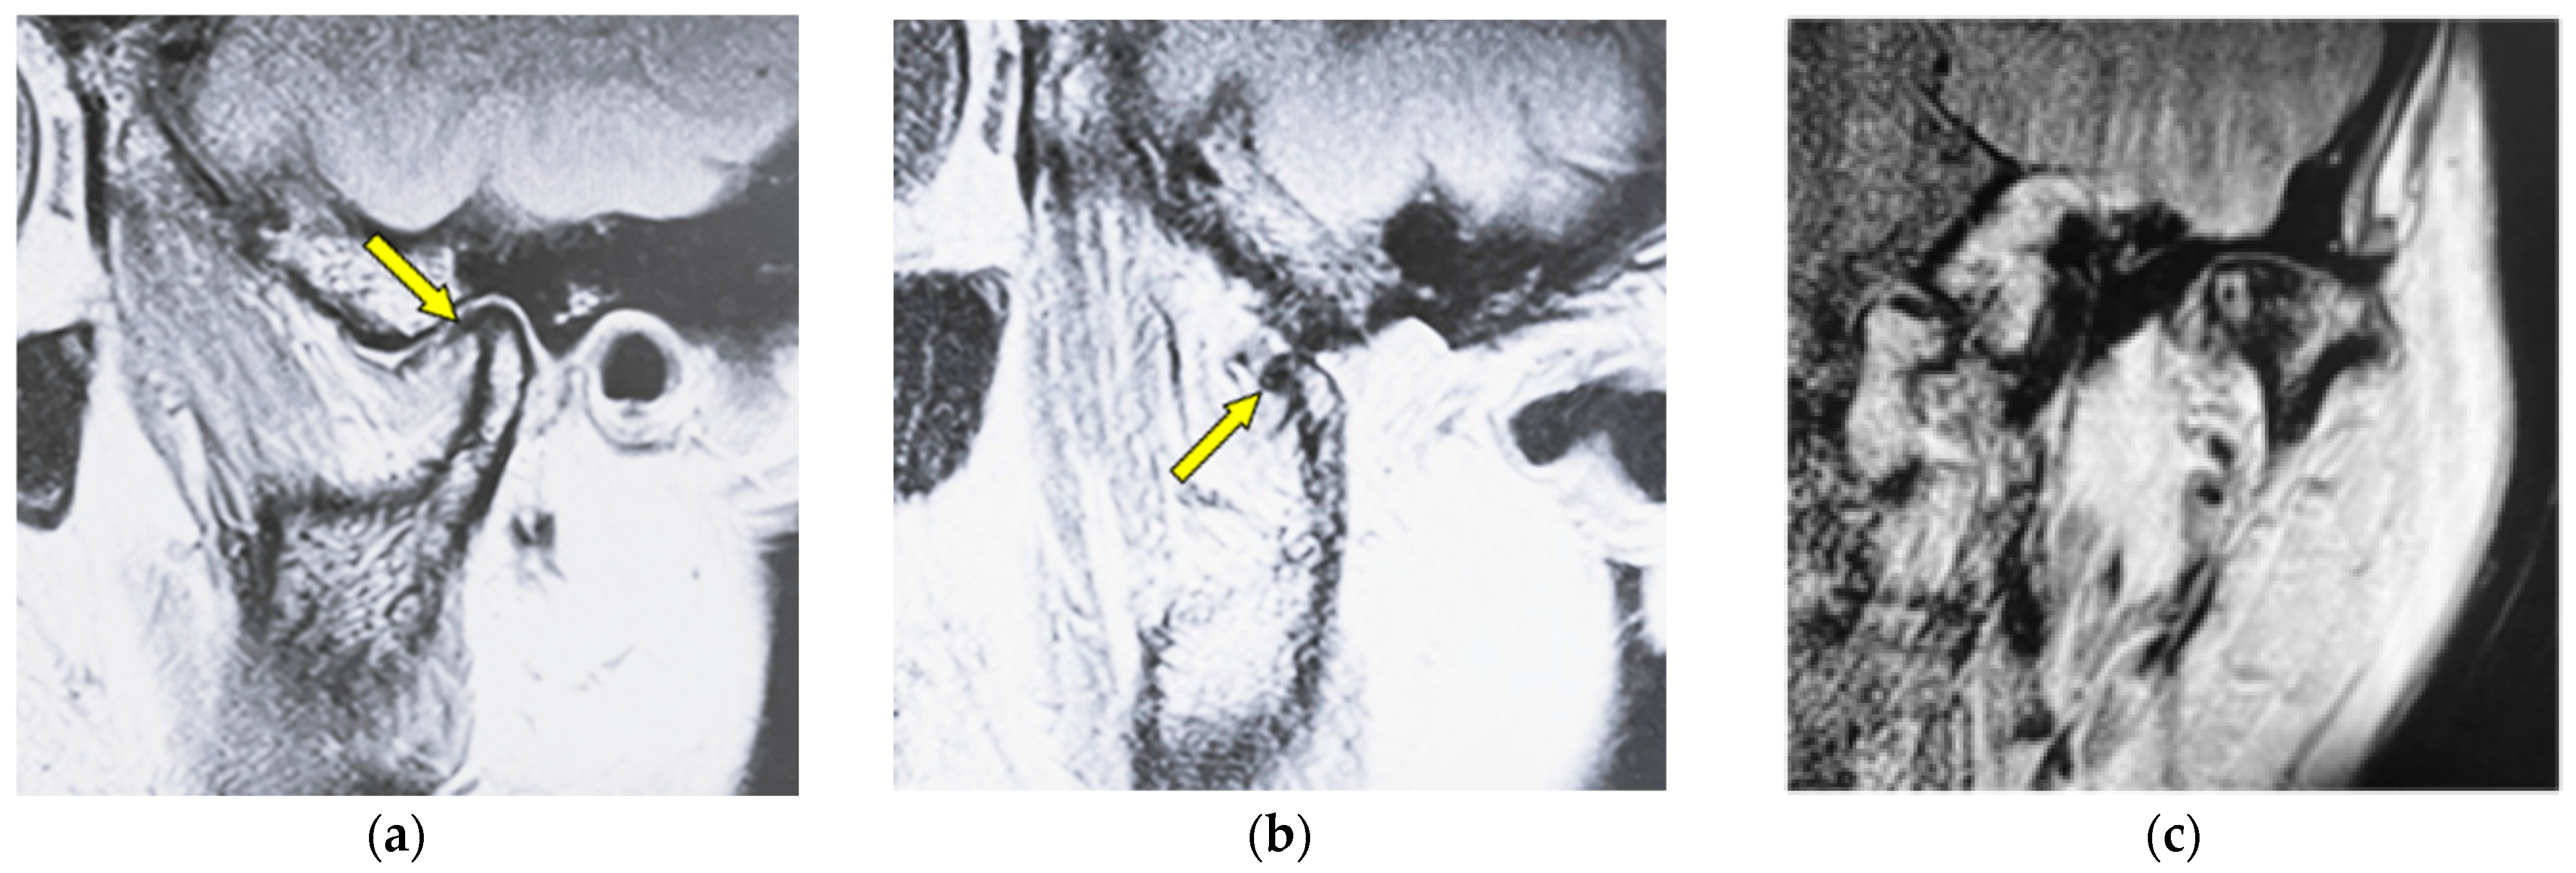

| Osteophyte | Local forward outgrowth of the condyle bone with an acute angle from the top of the head of the mandible |